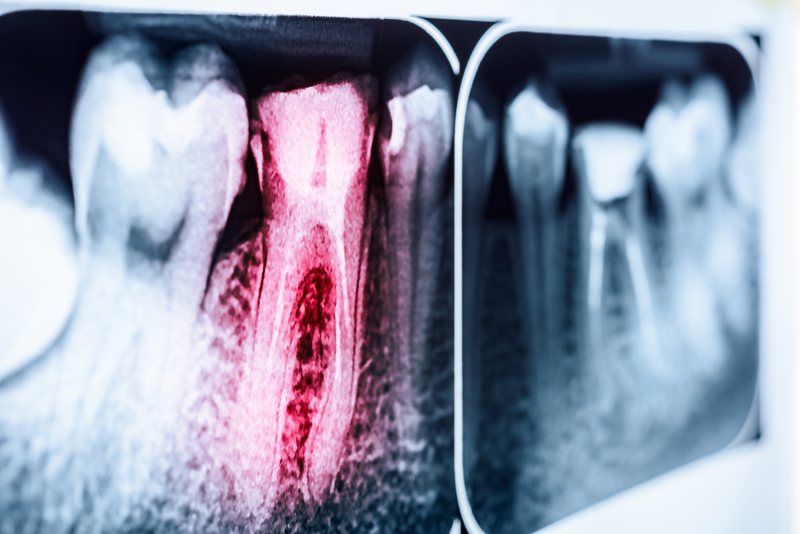

冠心病常見的發生原因,專家們都會告訴你是來自於「遺傳、環境和人口因素、三高及吸菸」等因素有關,但是近年來發現動脈血管上的斑塊和身體發炎也有關係,到底是哪些物質引起身體出血炎症呢?口腔常見引起牙齦發炎(牙齦炎)和牙周炎的核型化膿桿菌,竟然也是導致心血管粥狀的主要因素之一。

他們從從參與者血液中C反應蛋白(CRP)水平的數據衡量他們體內的炎症反應,還檢測包括15種病毒、6種細菌和1種寄生蟲的22種人類病原體測試。測試的細菌之一有一種普遍存在人體的「核型化膿桿菌」,這個常見的口腔細菌可導致牙齦炎、牙周炎,過去還曾經有研究指出,這個細菌可能擴散到人體的腸道,甚至還可能擴及女性生殖道而引起發炎等疾病。

研究人員經由數據分析發現,無論以前感染或是現在感染核酸菌,都有使冠心病(CHD)發生的風險提升。研究人員推測,核型化膿桿菌可能以兩種方式對人體形成傷害,包括直接從口腔感染中引起體內產生全身性的發炎反應,或是該菌從口腔轉移到血管內,並直接附著在冠狀動脈的壁上,促使斑塊生長。